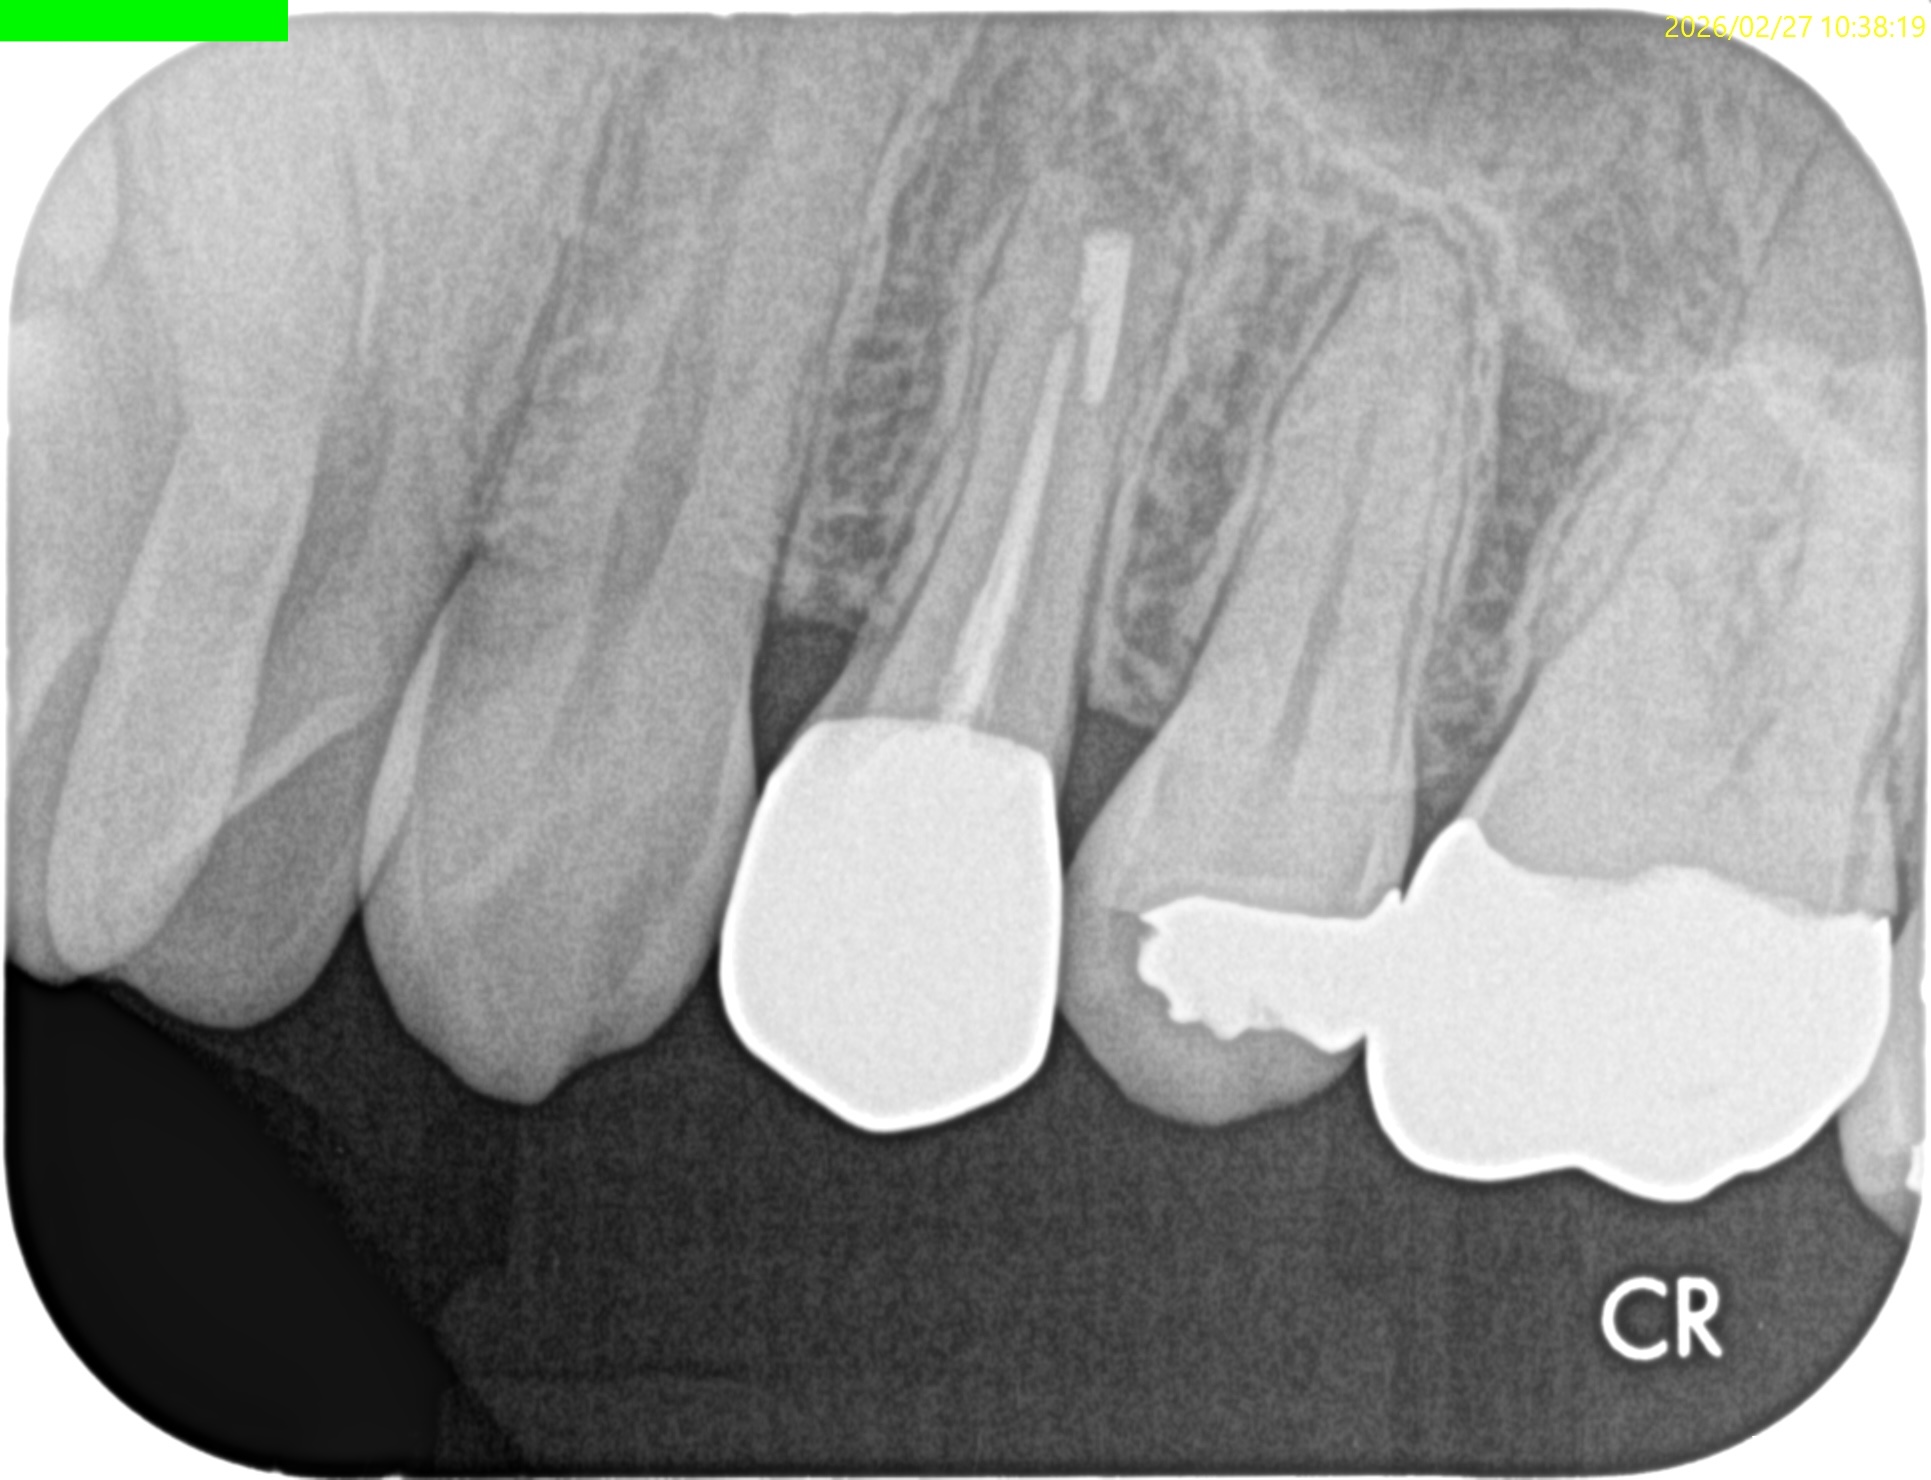

Pre-op Endo Test(2024.3.7)

#12 Cold++1/13, Perc.(+), Palp.(-), BT(-), Perio Probe(WNL), Mobility(WNL)

Pulp Dx: Pulp necrosis

Periapical Dx: Symptomatic apical periodontitis

Recommended Tx: RCT

#12 RCT(2024.3.7)

術後にPA, CBCTを撮影した。